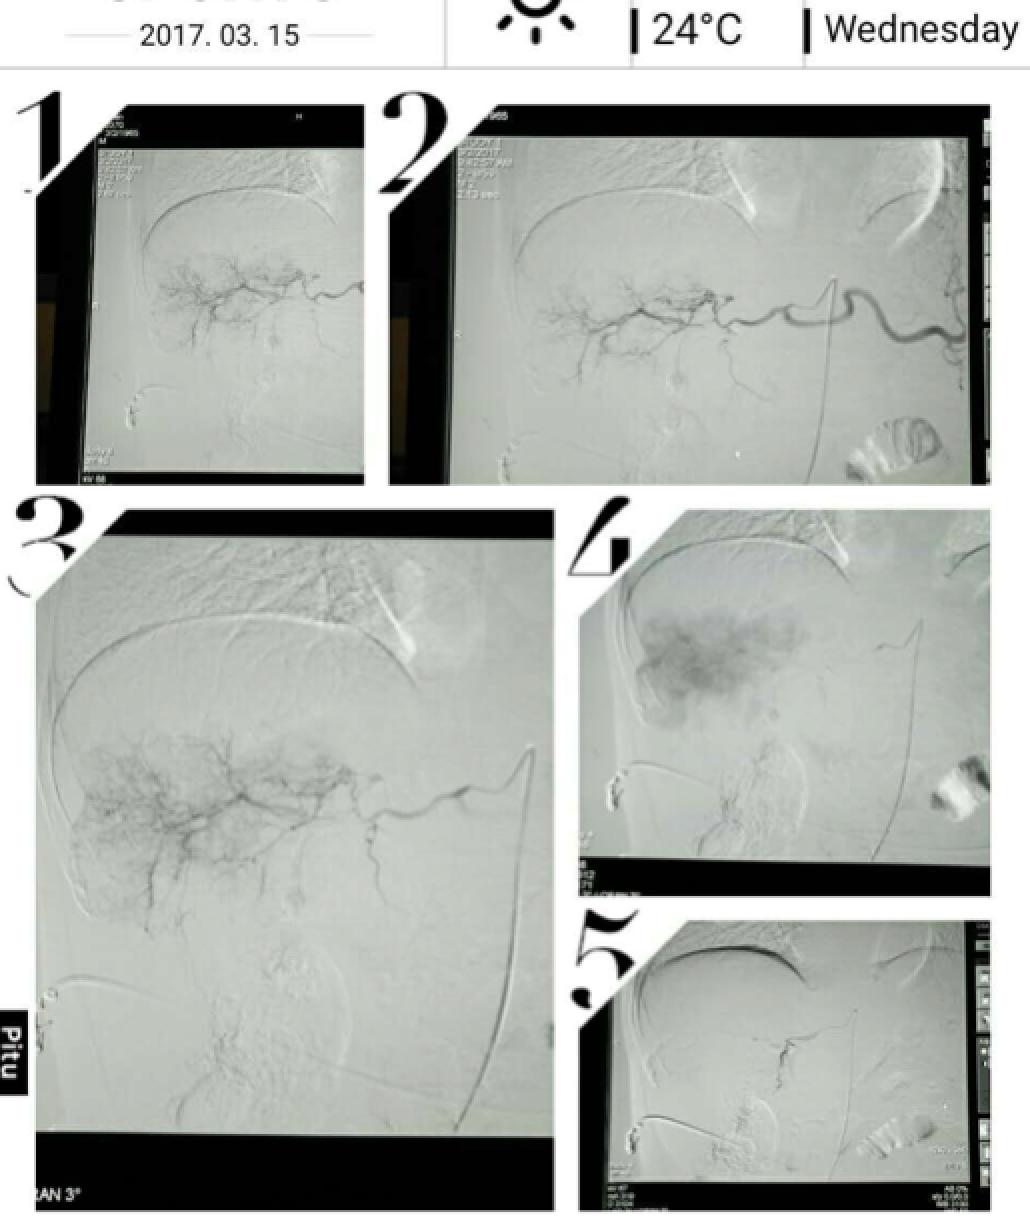

患者因纳差、烧心、腹痛、腹胀2月,于2016-01-17在某县人民医院行腹部CT示肝癌并门脉癌栓形成。分别于2016-01-22、2016-02-19于某市医院行两次TACE术(具体不详)。患者介入术后规律服用抗乙肝病毒、保肝、提高免疫力等药物治疗。2016-02-03至2016-04-30在某省立医院行5周期CIK免疫治疗。2016-05-18至2016-05-25于我院行射波刀治疗门静脉癌栓,具体放疗计划为:42Gy/7F。2016-06-24在我院行肝右动脉化疗栓塞术+肝右动脉灌注化疗术+间接门脉灌注化疗术,术中化疗总量,吡柔比星2mg、顺铂12mg、氟尿嘧啶250mg。分别于2016-05-10、2016-05-27、2016-06-13、2016-07-01、2016-07-27、2016-08-22、2016-09-19、2016-10-07、2016-10-19、2016-11-18、2016-12-18、2017-02-18行12周期免疫治疗。自2016-05-12起患者间断口服靶向药物阿帕替尼250-500mg/d,血压维持在220-130/95-70mmHg,血压升高期间伴上腹部不适,左侧为著,并向腰背部放射,偶尔反酸、烧心,剑突下疼痛,口服抑酸剂或进食后缓解,临床诊断为十二指肠溃疡,目前口服奥美拉唑、马来酸依那普利、氢氯噻嗪等药物对症降压。2017-03-02于我院行第二次肝右动脉化疗栓塞术+肝右动脉灌注化疗术+间接门脉造影术+肠系膜上动脉灌注化疗术。术中化疗总量,洛铂10mg、氟尿嘧啶500mg、吉西他滨400mg。目前间或皮下注射胸腺法新、重组人干扰素α-2b提高免疫力及慢性乙型病毒性肝炎治疗效果。

患者相关影像资料

4. 2017-3-15 DSA造影图中显示肿瘤组织血供一般,也未见癌栓显影,说明肿瘤组织或癌栓血供一般,也可能是靶向药物+栓塞化疗后,主要供血血管已闭塞,继续栓塞治疗效果有限。